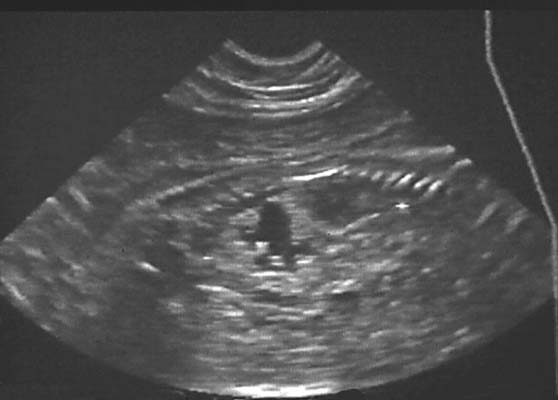

Boules de Gui